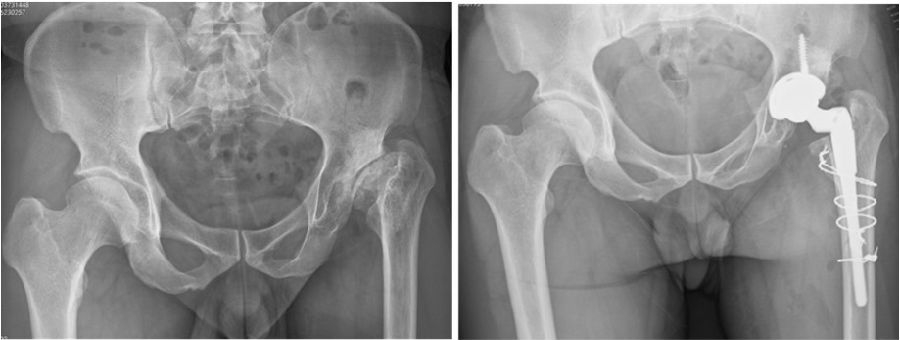

③近端的重建:纠正性截骨,短缩截骨。

股骨截骨的不同方法:

股骨近端截骨重建——截骨方式:横形、斜形、阶梯式及双V形截骨

优点:不改变股骨近端的解剖,保持臀中肌附丽点完整,截骨后能矫正股骨的前倾角,是较为理想的股骨缩短方法。

缺点:①骨折——截骨两端捆钢丝;②截骨端不稳定,术后骨折不愈合——足够长的远端固定型非骨水泥型假体或组配型假体,假体长度足够,避免型号过小,必要时使用骨板加强固定;③失血多、时间长。